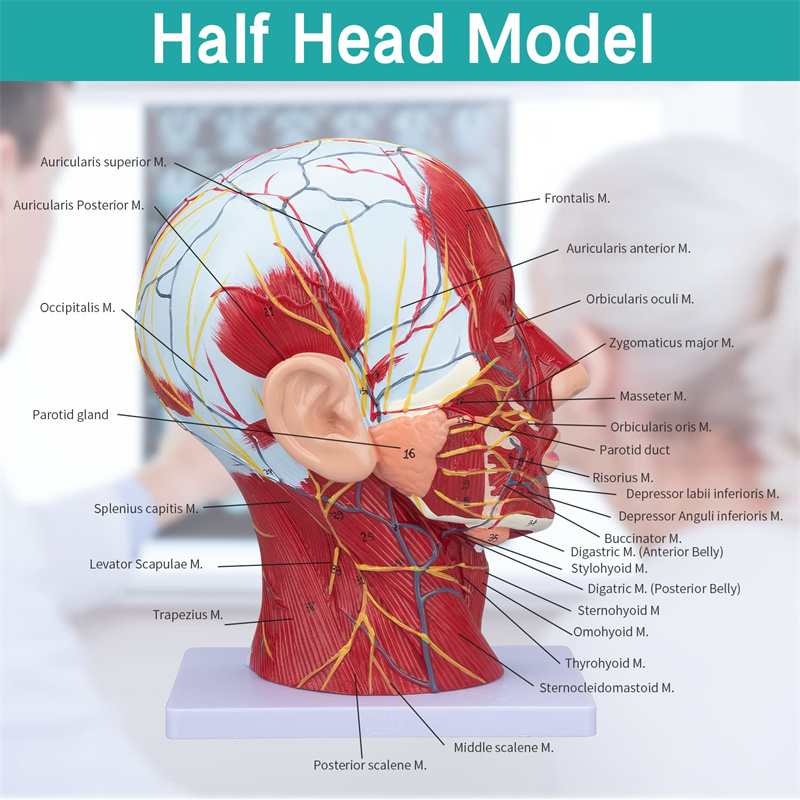

【Mudell tal-muskolu newrovaskulari superfiċjali】 Dettaljat ħafna, numri mmarkati, li jistgħu jinqalgħu, japprofondixxu l-fehim tal-muskoli superfiċjali, bastimenti, nervituri u l-istrutturi interni tar-ras u l-għonq. Arterja ħamra, vetta blu, isfar-nerve.

【Karatteristiċi】 Juri l-muskoli superfiċjali tal-wiċċ espost; il-bastimenti tad-demm superfiċjali u n-nervituri tal-wiċċ u l-qorriegħa; l-istrutturi ta 'ġewwa tal-glandola parotida u l-passaġġ respiratorju ta' fuq; L-istruttura tas-sezzjoni trasversali sagittali tas-sinsla ċervikali.

Dan il-mudell juri dettalji tal-għonq tar-ras tal-lemin u s-sezzjoni sagittali tan-nofs tal-bniedem. inkluż is-superfiċjali

muskoli tal-wiċċ espost; il-bastimenti tad-demm superfiċjali u n-nervituri tal-wiċċ u l-qorriegħa; l-istrutturi ta 'ġewwa

tal-glandola parotida u l-passaġġ respiratorju ta 'fuq; L-istruttura tas-sezzjoni trasversali sagittali tas-sinsla ċervikali.

Il-mudell wera l-morfoloġija lokali tas-sezzjonijiet sagittali medjali u laterali tar-ras u l-għonq u l-istrutturi vaskulari u tan-nervituri tiegħu, b'total ta '100 indikatur tas-sit.

Dan il-mudell huwa mudell ta 'muskolu newrovaskulari superfiċjali ta' ras u għonq naturali, komponent 1, li juri d-dettalji tar-ras tal-lemin u l-għonq u s-sezzjoni sagittali medjana, inklużi l-muskoli superfiċjali esposti tal-wiċċ, bastimenti superfiċjali tal-wiċċ u l-qorriegħa, in-nervituri u l-istruttura medjali tal-glandola parotida u l-passaġġ respiratorju ta 'fuq, u l-istruttura tas-sezzjoni sagittali tas-sinsla ċervikali